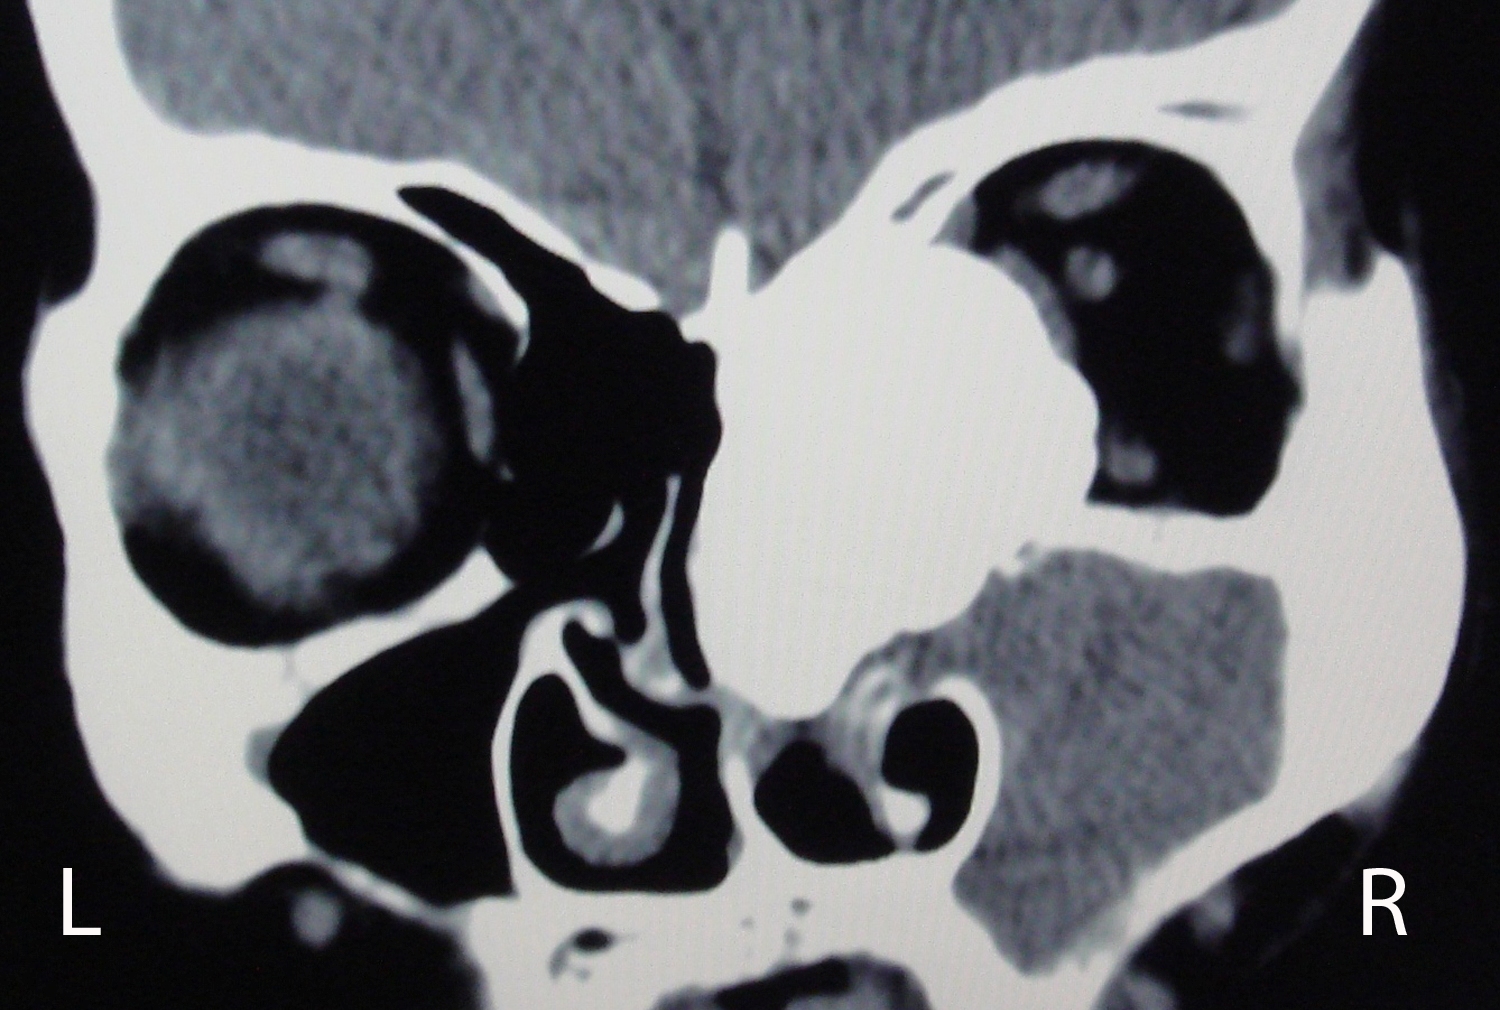

Osteoma is the most frequent benign tumor of paranasal sinuses. Usually osteomas are asymptomatic and discovered incidentally during radiological imaging for other reasons. A giant osteoma with intraorbital extension is rare. Plain radiograph may be useful; however CT scan is the best modality of investigation for diagnosing and treatment planning. In asymptomatic osteomas, serial follow-up can be done. Surgery is performed in the presence of symptoms and signs. We report a case of 60 years old woman with a large osteoma of right ethmoid sinus extending into the ipsilateral orbital cavity.